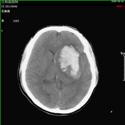

1).硬膜外血肿 术前 术后